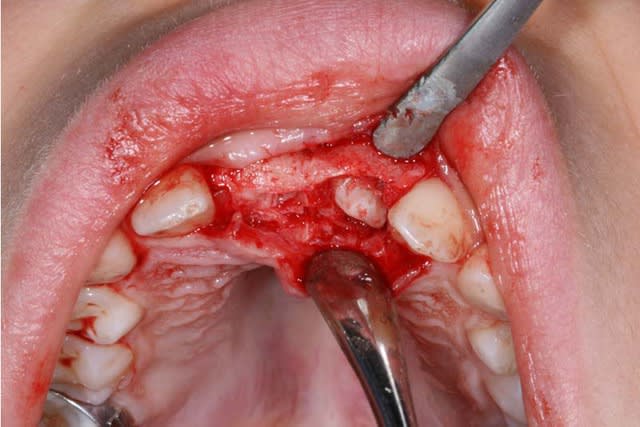

La chirurgie est décidée : ablation des odontomes, ce qui va permettre l’éruption des centrales

@+ Bjc.

Seule la 11 arrive sur l’arcade

Il faut donc faire une 2° chirurgie et coller un anneau de traction

Je décide faire moi-même, la 2° chirurgie

la 21 est en placement, sans trop de Pbs.